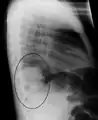

A black and white X-ray picture showing a triangle white area on the left side. A circle highlights the area.